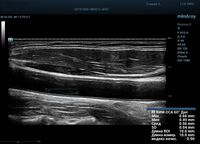

На сегодняшний день измерение IMT происходит автоматическим путем при использовании функции AUTO-IMT. Необходимо указать прибору зону интереса, стандартной длиной (1 см), в которой происходит отслеживание кромок и выдача максимального, среднего и минимального значения.

УЗИ аппараты компании Mindray среднего, экспертного и премиального класса снабжены данной функцией и позволяют контролировать не только полученные значения, но и оценить точность измерения кромки в конкретной зоне по индексу качества. Используя индекс качества, легко решить, можно ли использовать полученное значение.

Форма отчета стала удобной: в единой таблице сводятся измерения левых и правых артерий, указываются все значения с автоматическим расчетом общего среднего показателя. Если один из показателей измерения резко выбивается и считается недостоверным – его можно исключить из расчета.